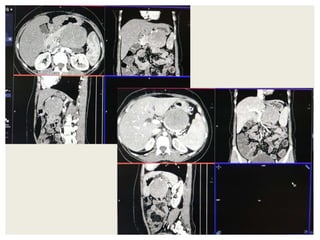

CASE1

DIFFERENTIALS

1. Neurogenic tumor possibly neurofibroma

• Age of presentation

• Well defined hypodense solid lesion

• Mild homogeneous enhancement

• Points against: Beak sign with pancreas

2. Pancreatic neuroendocrine tumor

• May present as hypoenhancing mass rarely

• Points against: Age, clinical presentatation and enhancement

characteristics

Most likely diagnosis-

Retroperitoneal Neurogenic Tumor possibly

Neurofibroma

CASE2

Diagnosis Points in favour Points against

Retroperitoneal

sarcomas

• Leiomyosarcoma

/Undifferentiated

Liposarcoma

• MFH

Age and clinical

presentation

Imaging features

(Large ill defined

heterogeneously

enhancing lesion

with areas of

necrosis)

No fat density/

calcification

No calcification

GIST Age

Biopsy:

 Poorly differentiated Leiomyosarcoma